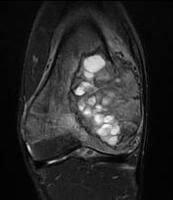

MRI

Usually difficult to determine UBC from ABC

- cystic lesions

- haemosiderin content - low to intermediate signal on T1 and T2

- borders and septae enhance with contrast

Fluid - Fluid levels

- due to sedimentation of RBC's & serum within the cavities

- patient must remain motionless for 10 minutes prior to the scan being performed

- allows time for sedimentation

- can also be seen in UBC